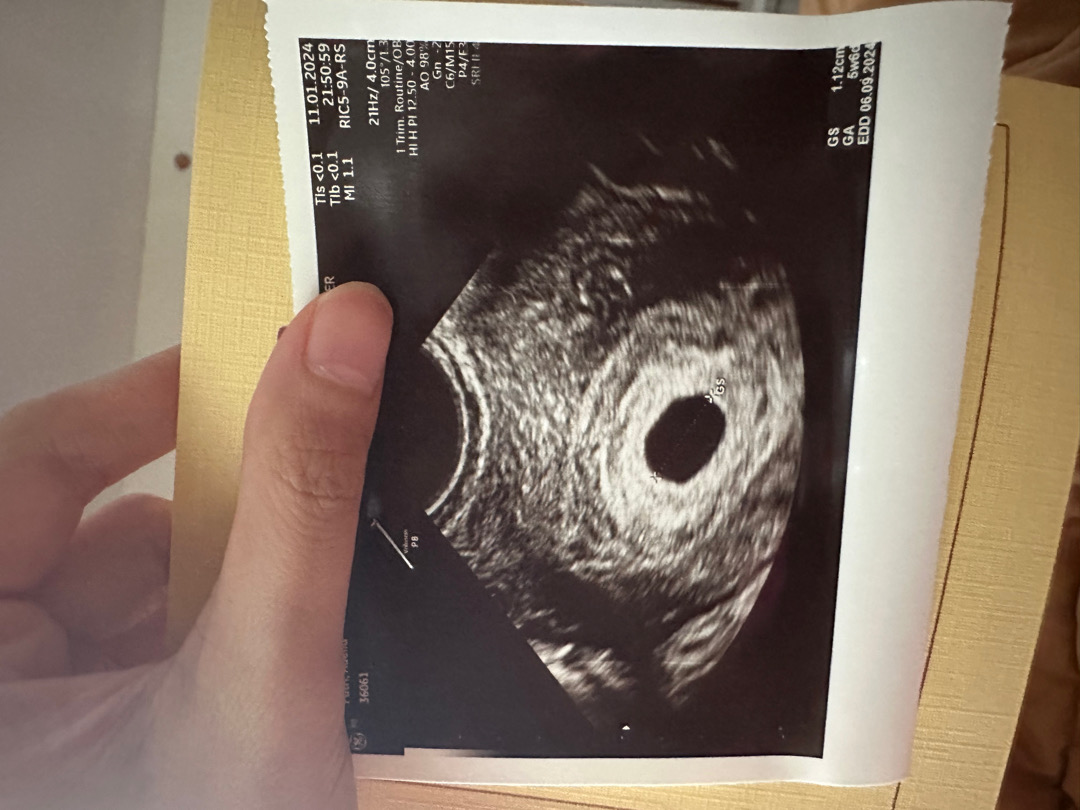

Usg 7w1d tetap masih keliatan kantung melaluin program IVF

Hii bund.. Sedih sekalii rasanya hasil usg saya masih sama seperti minggu kemarin:( Hancurr hati saya. Melalui program IVF ini banyak sekali efforts lebih yang sudah saya dan suami lakukan :( Dokter bilang “ minggu depan kesempatan terakhir ya, jika belum terlihat juga, terpaksa kita bersihkan “ Jujur saya takut sekali.. Saya tidak ada keluhan sama sekali. Tidak pernah ada flek. Dan sudah mulai mual dan muntah di pagi hari. Bagaiman ya bun :( saya sangat terauma untuk usg lagi dan sangat takut